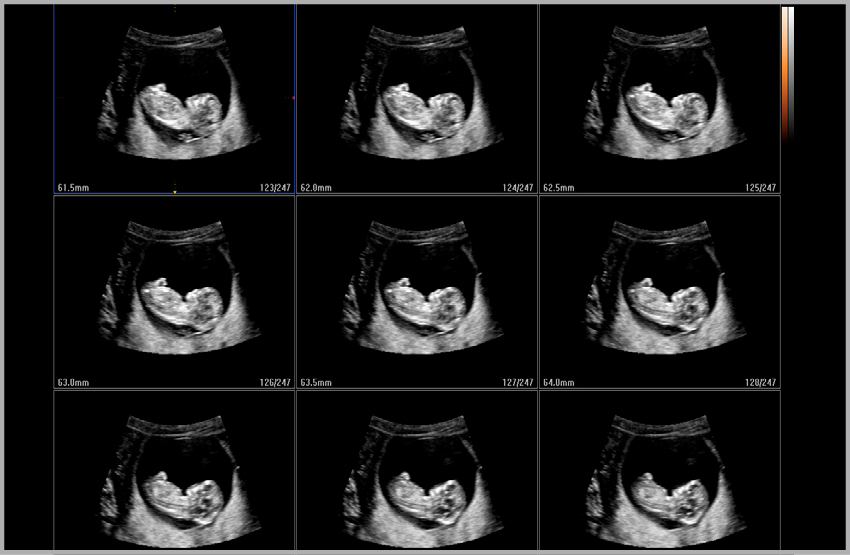

5D NT™

With Samsung's 5D NT™ , operator dependency can be reduced for the first trimester fetal nuchal translucency (NT) measurement. 5D NT™ allows the user to obtain the true mid-sagittal plane automatically by rotating and auto-zooming the image. This advanced technology is especially useful when facing difficult cases involving fetal position.